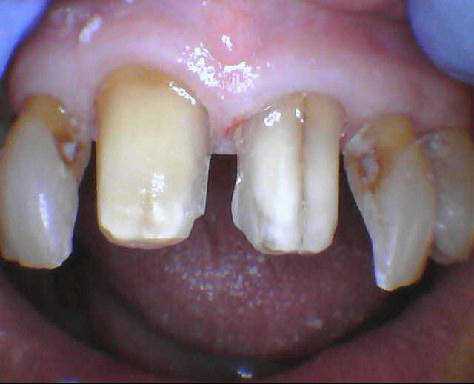

apres avoir lui avoir reglé la parafonction , , cette pré-mamie me demande de faire quelque chose pour ses fêlures pas jolies .

si je lui fais 2 facettes , comment gerer le prov ????

des idées sur la forme de préparation ?